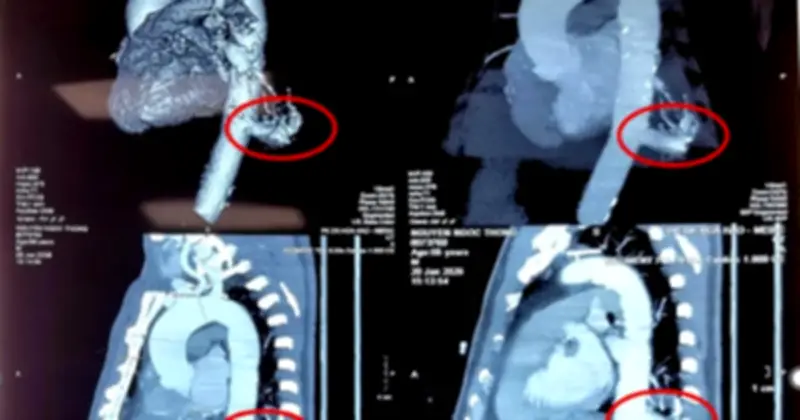

Bệnh nhân là ông N.N.T (56 tuổi, ngụ tại Tây Ninh) đã tình cờ phát hiện tổn thương ở thùy dưới phổi trái khi đi khám sức khỏe tổng quát. Tại Bệnh viện Bình Dân, các bác sĩ chẩn đoán ông mắc phổi biệt lập nội thùy với khối kích thước 23 mm × 26 mm.

Điểm đặc biệt nguy hiểm là động mạch nuôi khối này xuất phát trực tiếp từ động mạch chủ xuống với đường kính lên tới 17 mm - một kích thước rất lớn và tiềm ẩn nhiều rủi ro nếu không được điều trị kịp thời. Kết quả chụp MSCT ngực xác nhận phổi biệt lập nội thùy trong thùy dưới phổi trái, có nhánh mạch máu nuôi lớn xuất phát từ động mạch chủ ngực.